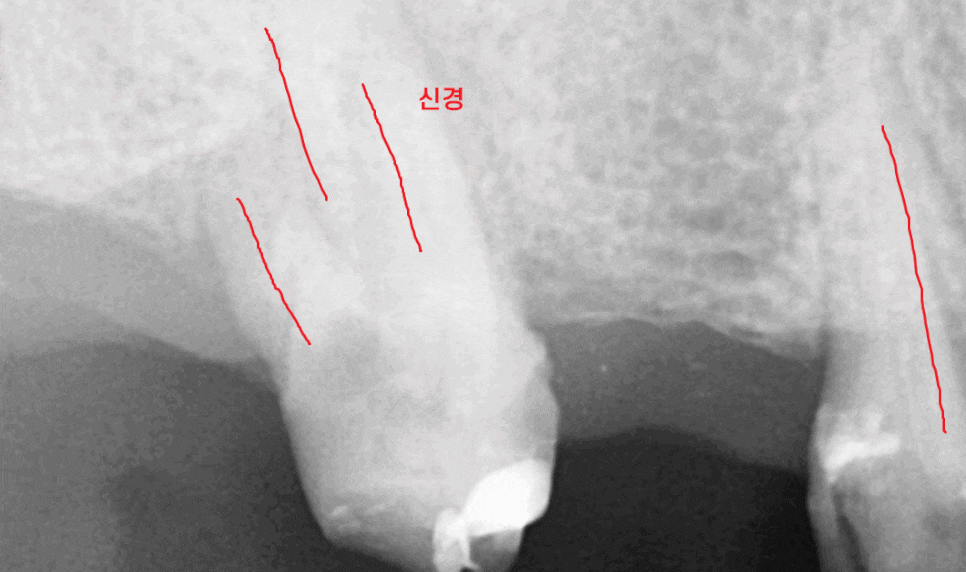

풍산동 치과에서 ct를 찍어보니

뿌리 흡수도 심하고

갈라지는 부분에 뼈도 많이 녹아있었거든요.